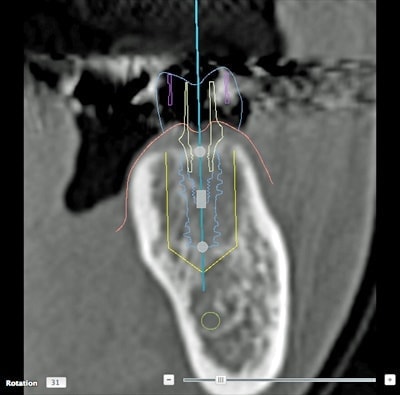

インプラントとは、顎の骨に人工歯根となる金属を埋め込み、それを土台にして、天然の歯と同じような人工の歯を取り付ける治療方法です。

埋め込む金属に生体との親和性が高いチタンが使われる事が多く、チタンは長年の臨床研究でインプラントの素材として最も安全であり、また顎の骨としっかり結合することが確認されています。

天然歯のような見栄えだけでなく、これまでの入れ歯やブリッジでは満足することが難しかった「食べる・話す」という機能も回復できます。

インプラントは周りの歯を傷つけず、残った歯への影響が少ないため、自分の歯を多く残せます。

また顎の骨がやせるのを防げる効果もあります。

食べ物のカスが挟まったり、留め金が見えるといったこともないので、衛生面や見た目からも、天然歯自分の歯と同じようにきれいで美しい状態を保てます。